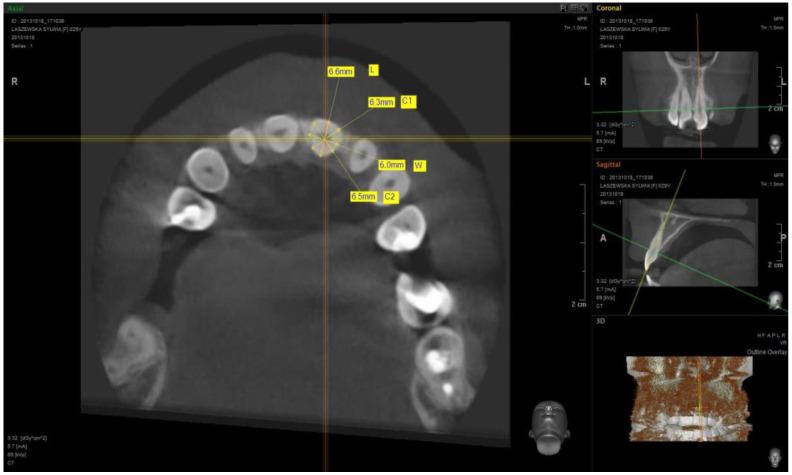

The study used cone-beam computer tomography (CBCT) scans of 51 patients. The measurements of the maxillary teeth (central incisor, lateral incisor, canine, first premolar, and first molar) were performed from cross-sections of the individual teeth at the transition zone to design a custom anatomic healing abutment milled from zirconium and luted to the non-index Ti-base.

本研究使用了51例患者的锥形束计算机断层扫描(CBCT)图像。从各颗牙齿在过渡区的横断面测量上颌牙齿(中切牙、侧切牙、尖牙、第一前磨牙和第一磨牙),以设计定制的解剖型愈合基台,该基台由锆铣削而成并粘结至非索引钛基台上。